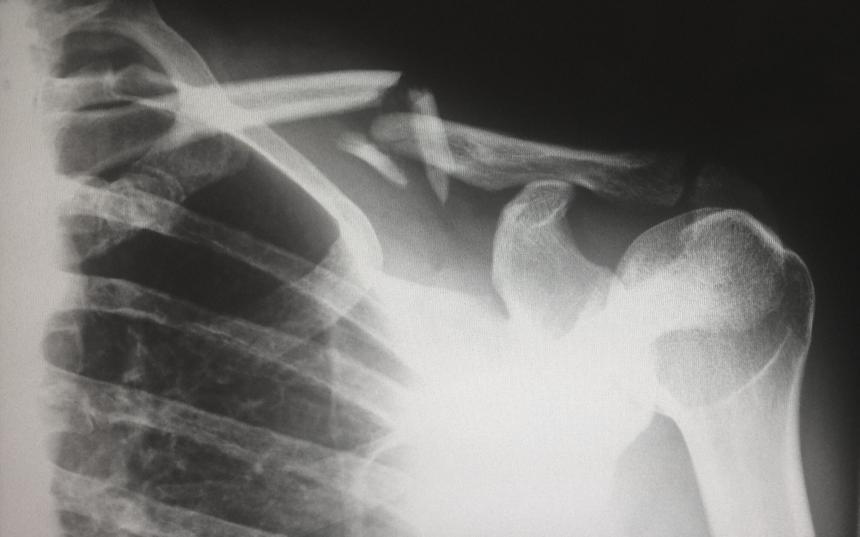

Группа учёных из Института высокомолекулярных соединений, НИЦ «Курчатовский институт», разработала новые полимерные материалы, включающие органические наночастицы. Эти материалы могут быть использованы для создания имплантатов, способствующих восстановлению костной ткани. Модификация материала позволяет стимулировать рост клеток окружающих тканей и образование новых связей с костью. По мере времени, такие имплантаты полностью растворяются, а новая ткань заменяет дефекты.

Руководитель лаборатории Института, Евгений Коржиков-Влах, подчеркнул, что эти свойства материала способствуют естественному восстановлению костной ткани. Результаты экспериментов на животных подтвердили эффективность процесса восстановления. Учёные утверждают, что их разработка будет полезной в случаях, когда необходимо восстановить значительные объёмы костной ткани у пациентов.